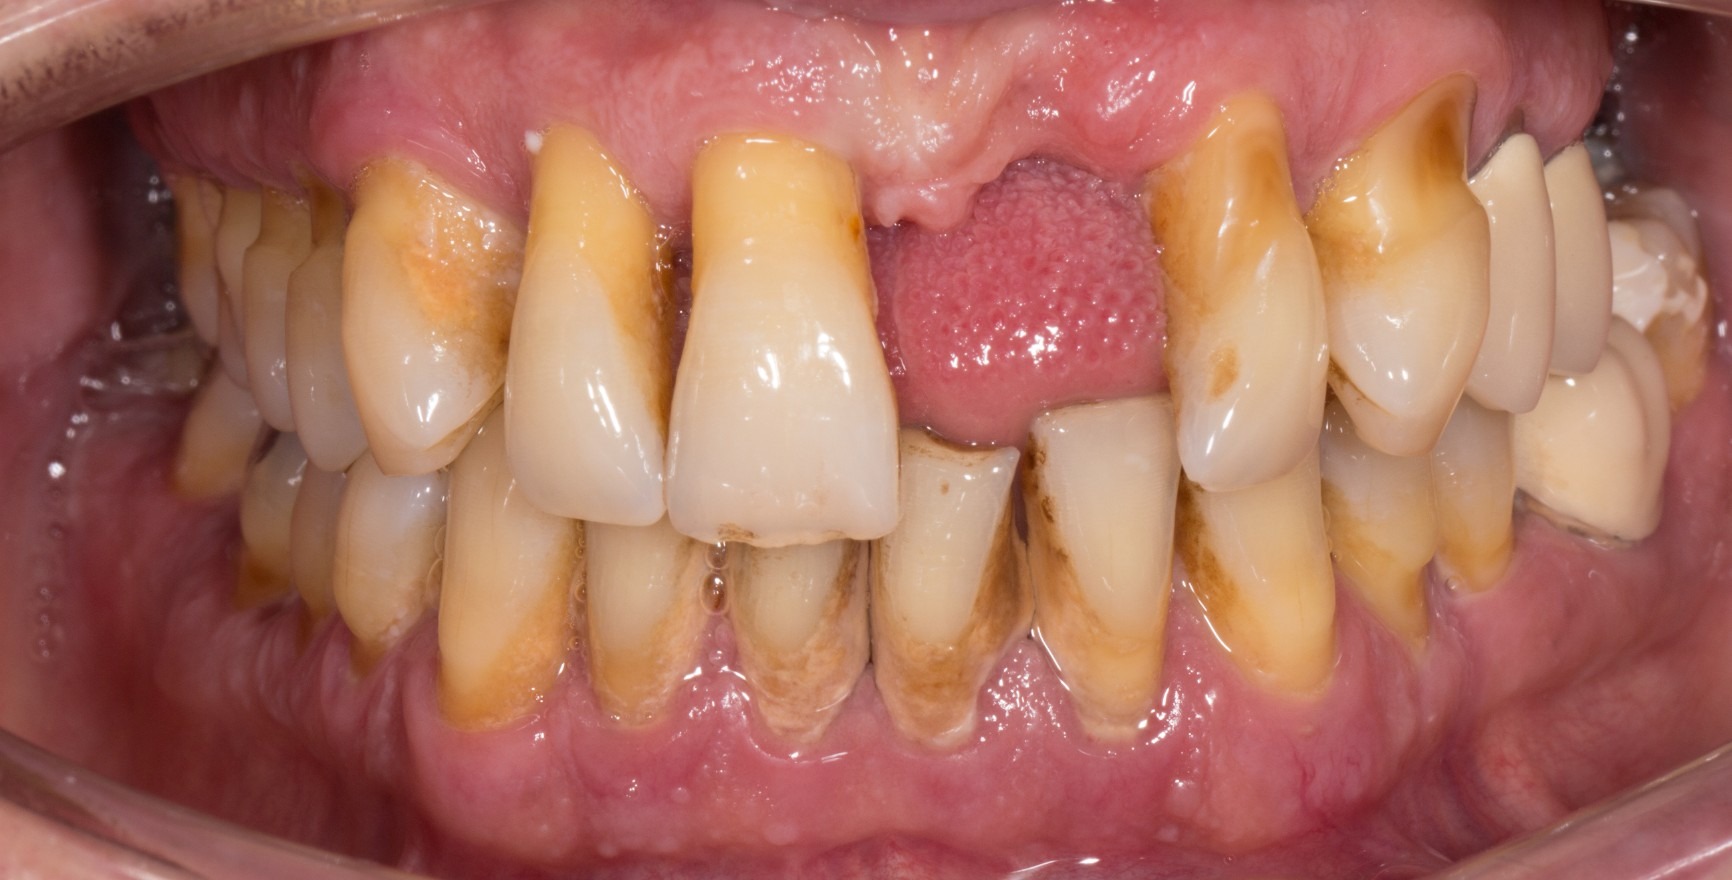

Pour la première fois, le nouveau schéma de classification des maladies parodontales, présenté en juin 2018, contient une définition du concept de santé parodontale clinique (Lang & Bartold, 2018). Même dans des conditions d'hygiène optimales, une petite quantité de biofilm bactérien est présente dans le sillon gingival. Une absence totale de bactéries n'est pas possible dans les conditions cliniques. La réponse histologique à ce phénomène est un infiltrat sous-épithélial limité de granulocytes neutrophiles (PMN). Cependant, si l'homéostasie est maintenue entre le biofilm et une petite quantité d'infiltrat de PMN, cet état est considéré comme l'expression d'un contrôle immunologique et donc comme un processus physiologique et non pathologique (inflammatoire) (Brecx et al., 1987a+b). La charge microbiologique et les facteurs de l'hôte déterminent si l'état de santé parodontale clinique se maintient. Localement, ils peuvent conduire à une accumulation accrue de biofilm (par exemple, restaurations dentaires inadéquates ou positions dentaires défavorables) ou ils peuvent affecter la réponse immunitaire (par exemple, maladies systémiques).

On distingue l'état de santé parodontale clinique d'un parodonte intact de celui d'un parodonte réduit déjà affecté par une perte d'attache clinique. Cette perte d'attache peut se produire :

à la suite d'une l'inflammation au cours d'une parodontite. La santé parodontale clinique décrit alors un état stable après l'achèvement réussi du traitement parodontal.

Le critère clinique est toujours l'absence de saignement lors d'un sondage minutieux (saignement au sondage = BoP). Une distinction est faite entre un diagnostic spécifique au site/à la dent avec un résultat BoP négatif au site de mesure correspondant, et un diagnostic au niveau de la dent ou du patient, pour lequel une valeur seuil d'un BoP ≤ 10 % répond toujours aux critères de santé parodontale clinique. La profondeur de sondage des poches ne doit pas dépasser 3 mm. Dans un parodonte réduit après un traitement parodontal, une valeur seuil de 4 mm est encore considérée comme un état stable (Matuliene et al., 2008).